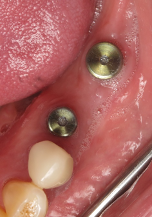

(3.) CBCT scan of tooth No. 12, exhibiting a retained root that previously received root canal treatment.

Figure 3

After a CBCT scan (Figure 3) and a digital impression were obtained for diagnosis and treatment planning, the DICOM file from the CBCT scan and the STL file from the digital impression were merged in a treatment planning software application for evaluation. A virtual crown was then created to facilitate a restoration-driven approach. The vital structures and osseous anatomy were identified, and the implant position was planned virtually (Figure 4 and Figure 5).